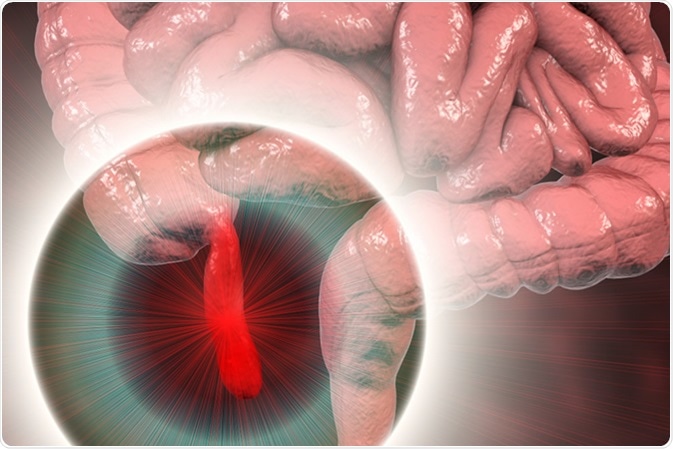

Appendicitis

Appendicitis refers to the inflammation of the appendix, a small and thin pouch connected to the colon. It can become inflamed and lead to severe pain. In severe cases, an inflamed appendix may rupture, leading to peritonitis, a serious infection of the inner lining of the abdomen. The most common symptom of appendicitis is pain that begins near the umbilical area and moves down into the right side of the lower abdomen. It gets worse in a matter of hours, but twinges of sharp pain even before that, when moving around or taking deep breaths.

Acute appendicitis, 3D illustration showing inflammed appendix on the cecum. Image Credit: Kateryna Kon / Shutterstock